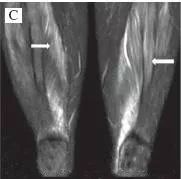

四、肌肉MRI:

四肢近端肌肉等出现炎性渗出表现。

五、肌肉活检行病理检查:

取近端肌肉如三角肌、肱二头肌,股四头肌等部位,有时候可结合肌肉MRI影像显示肌肉炎性渗出明显的地方取材,提高阳性率。